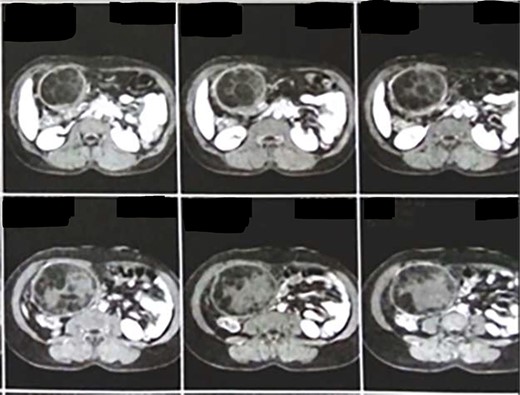

Our patient was a 39-year-old female Syrian refugee who presented with compressive symptoms since one month, i.e. right abdominal and epigastric pain along with discomfort. On physical examination, a large mass with mild tenderness was palpable in the upper abdomen. Her past history was unremarkable. Her hematological and biochemical parameters (including liver function tests) were within the normal range. The definitive diagnosis was made based on computed tomography (CT) scan findings; it showed a cystic mass (size: 17 × 11 cm) containing the characteristic small daughter cysts and with clearly delineated reactive caps (pericystic wall) consisting of fibrous connective tissue and calcification (Fig. 1). Her American Society of Anesthesiologists (ASA) physical status score was ASA I.

CT showing a cystic mass (size: 17 × 11 cm) containing the characteristic daughter cysts and with clearly delineated reactive caps (pericystic wall).